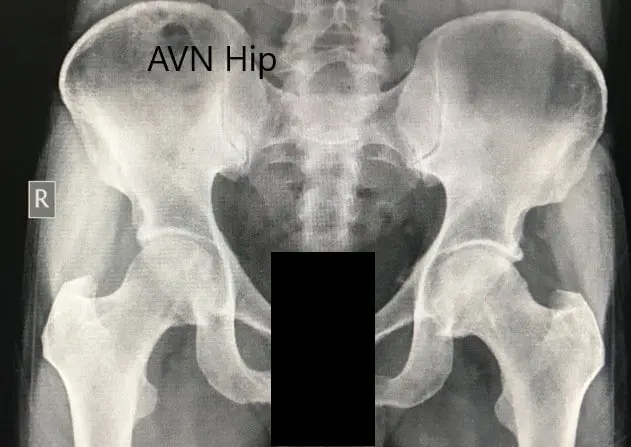

Imaging studies in the form of an X-Ray was obtained which suggested sclerosis of the bilateral head of the femur with acetabulum changes. An MRI was obtained which suggested avascular necrosis of both hips.

Preoperative X-ray of the pelvis with both hips in anteroposterior view showing AVN of the bilateral hips.